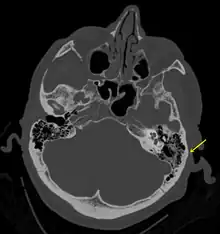

A subtle temporal bone fracture as seen on a CT scan | |

Basilar skull fractures include breaks in the posterior skull base or anterior skull base. The former involve the occipital bone, temporal bone, and portions of the sphenoid bone; the latter, superior portions of the sphenoid and ethmoid bones. The temporal bone fracture is encountered in 75% of all basilar skull fractures and may be longitudinal, transverse or mixed, depending on the course of the fracture line in relation to the longitudinal axis of the pyramid.[5]